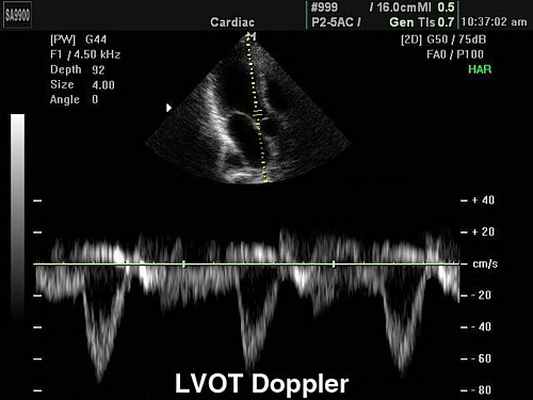

Непрерывноволновая допплер-ЭхоКГ у пациента с клапанным аортальным стенозом.

Слева: слабый допплеровский сигнал и малоинтенсивная граница спектра при нативной регистрации.

Справа: после усиления сигнала при помощи внутривенного введения Левовиста отчетливое выявление пикового градиента, равного 92 мм рт.ст. Трансторакальное исследование потока крови в легочных венах в режиме импульсно-волновой допплер-ЭхоКГ.

Спектральная допплер-ЭхоКГ может выявить объем, направление и тип потока крови. Данная методика необходима для обнаружения аномальных потоков крови (например, связанных с регургитацией) либо объемов (например, обусловленных стенотическими причинами). Допплер-ЭхоКГ не несет дополнительной информации о размерах и форме сердца и его структур.

Цветная допплер-ЭхоКГ в комбинации со спектральной и двухмерной допплер-ЭхоКГ позволяет более точно оценить размеры, форму сердца и его структур, также как объемы и направления потоков в области клапанов и выносящих трактов. Цвет используется для разграничения потоков крови; по соглашению красный поток, идущий к датчику, синий – в обратном направлении.